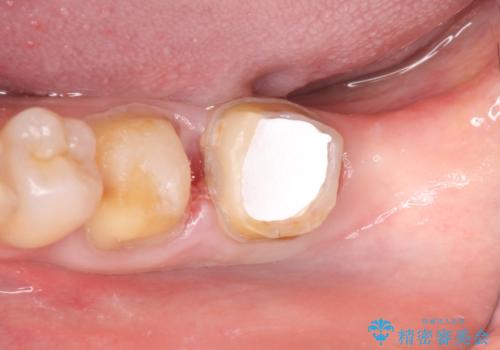

また左下6は遠心にあった歯茎より深い虫歯(縁下カリエス)の問題を解決するため、歯茎を下げる歯周外科手術を行いました。

歯周外科手術終了後、歯茎の回復を待ち左下6、7ともにオールセラミッククラウン(スタンダード)による補綴を行いました。

虫歯が進み歯茎より深くなってしまうと、虫歯を取り残してしまうリスク、樹脂の硬化の妨げ、補綴物の不適合、歯肉炎・歯周病のリスクの増大等様々な弊害が起こり得ます。

そのため当院では歯周外科手術(歯茎を下げる手術)や歯の挺出による、虫歯が歯茎より深いという問題の解決を推奨しております。